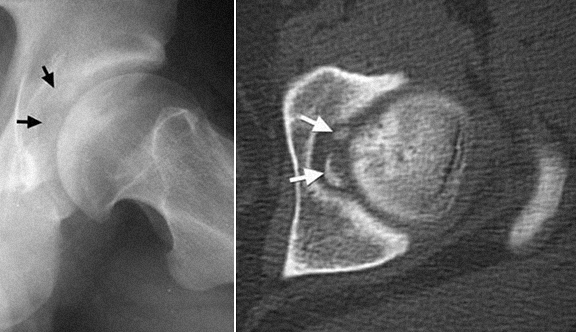

4 - Quisto intra-articular - exérese